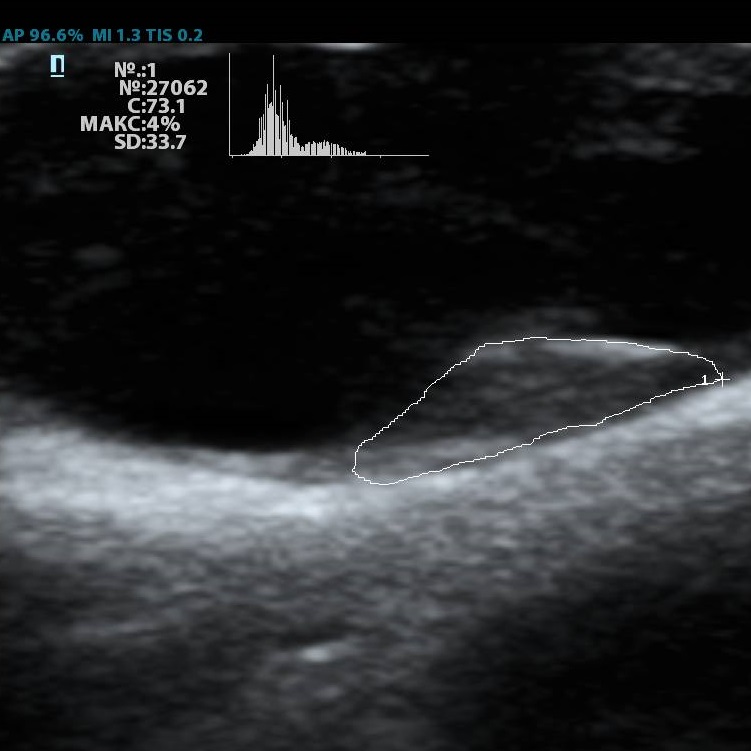

Помимо базовых целей по выявлению атеросклероза, бляшек, оценки кровотока и значимости стеноза, врачу ультразвуковой диагностики ставится и множество других задач при исследовании сонных артерий. Одна из них – оценка стабильности бляшки.

Ранее коллеги опирались на визуальную оценку, насколько бляшка гомогенная и какова её эхогенность. Есть ли в ней кальцинаты или анэхогенные участки. Для этого использовались международные классификации, с разделением среза бляшки по процентам – сколько гипер- и сколько гипоэхогенных зон. Такой метод  оценки до сих пор весьма популярен, однако он имеет минусы. Основной его минус в субъективности. Тяжело на глаз сказать, на 49,9% своей площади бляшка эхогенна или же на 50,1%, да и глаз у каждого человека несколько разный. Один специалист скажет – тут больше 50% гипоэхогенного, другой, что менее. Таким образом, метод сильно зависит от оператора – специалиста ультразвуковой диагностики.

Современное решение – компьютерный анализ структуры бляшки. Ультразвуковая система экспертного класса Mindray DC-8 способна провести программный анализ полученного изображения бляшки и дать количественную оценку её структуры. Для этого используется показатель GSM – Grey Scale Median. Прибор рассчитывает медиану по показателям серой шкалы в выделенной зоне и выдает данные в виде графика распределения эхогенности и числовых данных для количественной оценки. Таким образом, исследование становится более объективным и воспроизводимым, снижается зависимость от оператора (человеческого фактора).